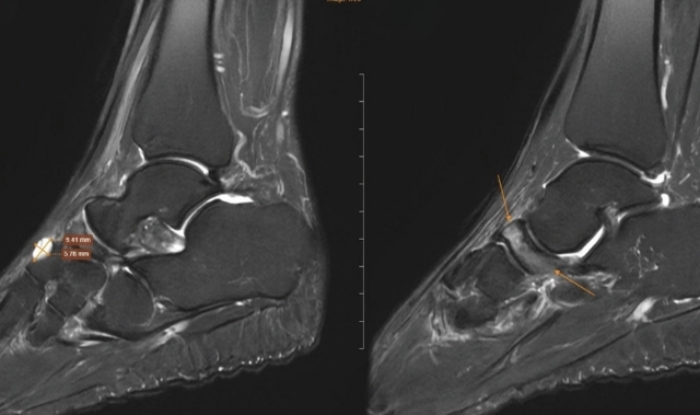

Người phụ nữ đau cổ chân kéo dài sau thời gian chạy bộ liên tục, kiểm tra phát hiện hội chứng hiếm khiến xương bàn chân xẹp, nguy cơ biến dạng vĩnh viễn.